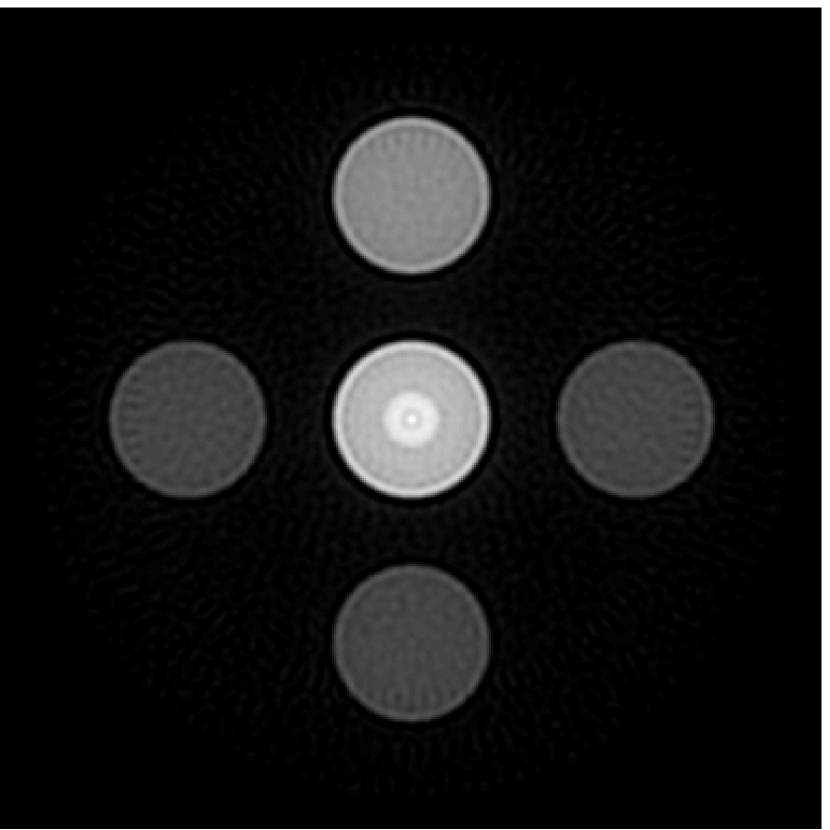

The numerical phantom shown in Figure 1(a) was employed. The phantom had a support area of mm2 and contained six uniform disks that were assigned different values of absorbed optical energy density.

A 2D circular measurement geometry was employed. transducers were evenly distributed on a ring of radius mm that enclosed the phantom. The SOS was assumed to be constant and set at mm/s. Since the simulated data were formed by use of the C-D imaging model in Eqn. (2), no inverse crime was committed. The components of this vector corresponded to equally spaced temporal samples over the interval s. Subsequently, the noiseless voltage vector was obtained by convolving the pressure data with EIR-1 in Figure 1(b).

The reconstruction region ( mm2) was represented by pixels with pixel size mm in each dimension. The initial guess of the EIR employed in the VP algorithm was different than the EIR that was assumed when generating the simulated data. This served to simulate a situation in which an experimentally measured EIR contained errors.

Each element in a real-world transducer array possesses its own EIR. In practice, the differences between the EIRs are sometimes neglected and an EIR corresponding to a single element may be used to represent all elements in the array. In some of the studies below, the EIR employed to initialize the VP algorithm (EIR-2 in Figure 1(b)) and the EIR employed to produce the simulated measurements (EIR-1 in Figure 1(b)) were experimentally measured from two different transducer elements in a circular transducer array (see Sec. VI-B). EIR-1 was measured by temporally integrating the PA signal produced by a point source positioned at the focus of the transducer. EIR-2 was measured by use of the method reported in [RNR2011]. In order to investigate the sensitivity of the VP algorithm to the initialization of the EIR, we employed different EIRs obtained by degrading EIR-1 as described later. When solving the sub-problem in Line-2 of Algorithm 1, was initialized as the zero vector. Algorithm 1 was terminated after 500 iterations, since it was observed that the changes in the reconstructed images with more iterations were negligible. When implemented by use of a single core of an Intel Xeon E5-2640 CPU, each iteration required approximately 7s to complete.

Figure 2(a) shows the image reconstructed by use of the conventional iterative method that utilized a system matrix based on EIR-2. Different values of the regularization parameter from the interval were considered. The reconstructed image with the value of that minimized the RMSE was chosen to represent the best performance of the conventional iterative method. Figure 2(a) and the profile in Figure 2(c) demonstrate that the use of an inaccurate EIR can result in strong artifacts and distortions in images reconstructed by use of the conventional methods.

When the VP algorithm was applied, different values of the regularization parameter from the interval and from the interval were considered. The image that minimized the RMSE was chosen and displayed in Figure 2(b). As revealed by this image and the profiles in 2(c), the VP algorithm yielded an image with fewer artifacts and distortions, and image fidelity was improved as reflected by the reduced RMSE.